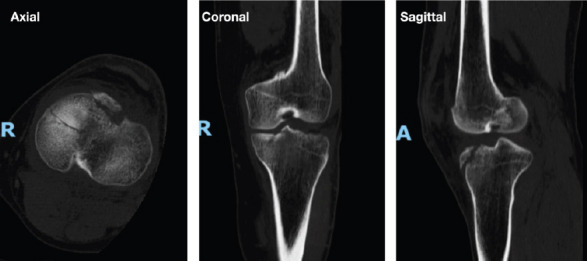

Case report: A 44-year-old medically free male sustained a hyperextension injury to his left knee after being kicked by a horse. Imaging showed an anteromedial tibial plateau rim fracture, as well as a fibular head fracture. Examination under anesthesia revealed a stable knee. Open reduction and internal fixation were conducted using a 3.5 locking compression plate L-shaped plate, and screws. Post-operative outcomes at 7 months of follow-up, the patients had complete knee mobility, no significant ligamentous damage, and returned to regular activities without discomfort.